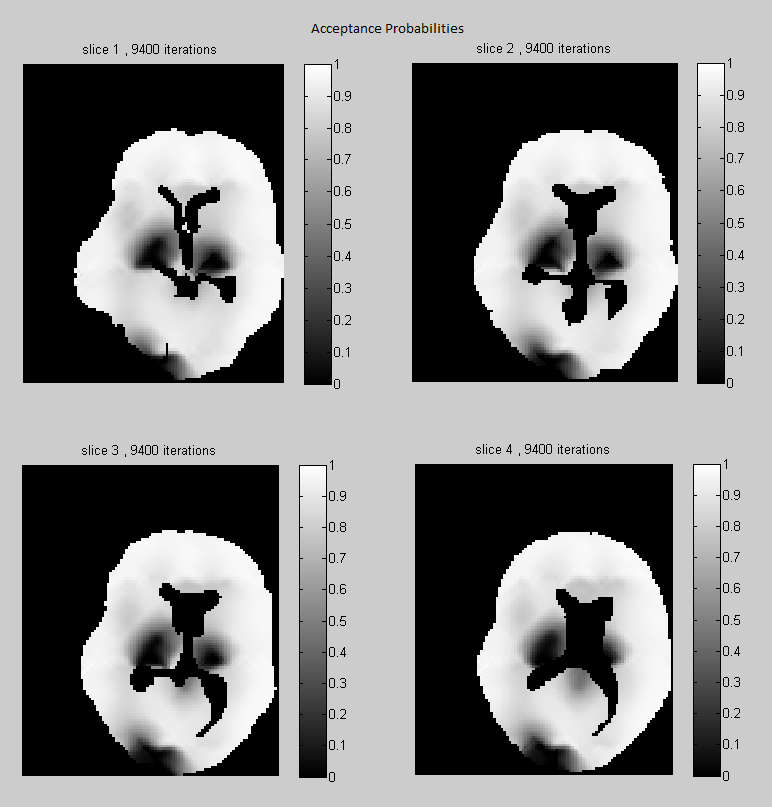

Acceptance probabilities

In Fig. 3 we show the acceptance probabilities for the Gibbs-Metropolis block update of the tensor parameters, estimated for each voxel under the regularized 2nd and 4th order tensor models. Note that, although we use large block updates with more than 300 voxels in each block, the acceptance probabilities are remarkably high in most of the voxels (see the histograms). It means that in most cases the our Gaussian approximation is very close to the exact full conditional distribution of the tensor parameters in a block. Note also that in Fig. 3(a) (which corresponds to 2nd order tensor model) there are some regions with lower acceptance probability. In such areas one should use update blocks of smaller size. These regions of lower acceptance probability are either artefacts, where the data are corrupted, or contain complex structures where the 2nd order tensor model does not fit well the data, and a higher order model would be more appropriate. We see two low acceptance probability regions situated symmetrically on the left and right sides of the ventricles. Anatomically this corresponds to the corona radiata where fiber bundles from multiple directions are crossing. By comparing with Fig. 3(b) we see that in these regions the acceptance probability improves under the (regularized) 4th order tensor model. For the diffusion model without regularization, the independent tensor updates have high acceptance probabilities at all voxels, under both 2nd and 4th-order tensor models (in 5).